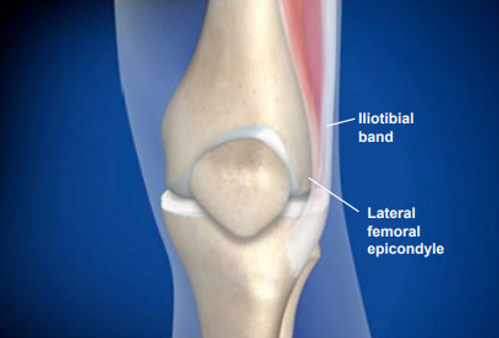

This condition is a painful inflammation of the iliotibial band, a thick, tendon-like portion of a muscle that travels from the hip down the outer side of the thigh to the knee. ITBS results in pain, aggravated by activity, that is usually felt on the outer side of the knee.

Iliotibial Band syndrome is caused by overuse of the iliotibial band, which stabilizes the knee. The iliotibial band glides back and forth over the lateral femoral epicondyle during walking or running, and this constant rubbing can cause irritation and inflammation. ITBS can be caused by poor training habits, such as inadequate stretching or running on a banked surface, or by abnormalities in the anatomy of the legs and feet.